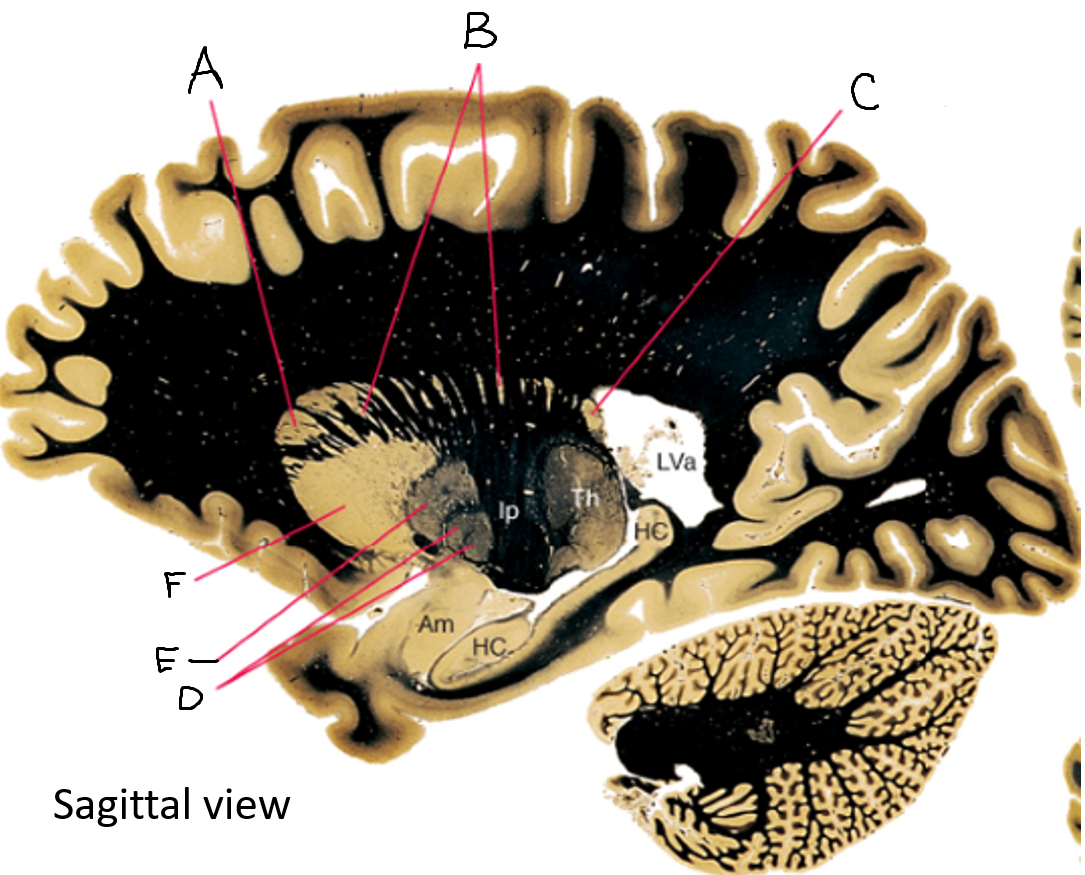

caudate nucleus head

A

Putamen

B

caudate nucleus tail

C

Lateral ventricle

D

caudate nucleus body

E

internal capsule

F